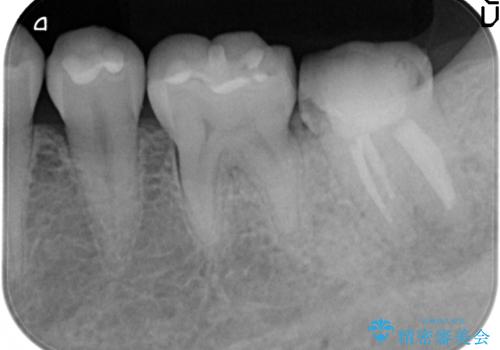

- 左下の一番奥の歯が時折激しく痛むので診て欲しいといらっしゃった方の症例です。以前に他院を受診したところ、そもそも被せ物を入れるスペースがないため抜歯しかないと言われたとのことでした。

診査の結果根尖病変を認めたため再根管治療を行った後に、被せ物を入れるスペースを作るため歯冠延長術を行いました。